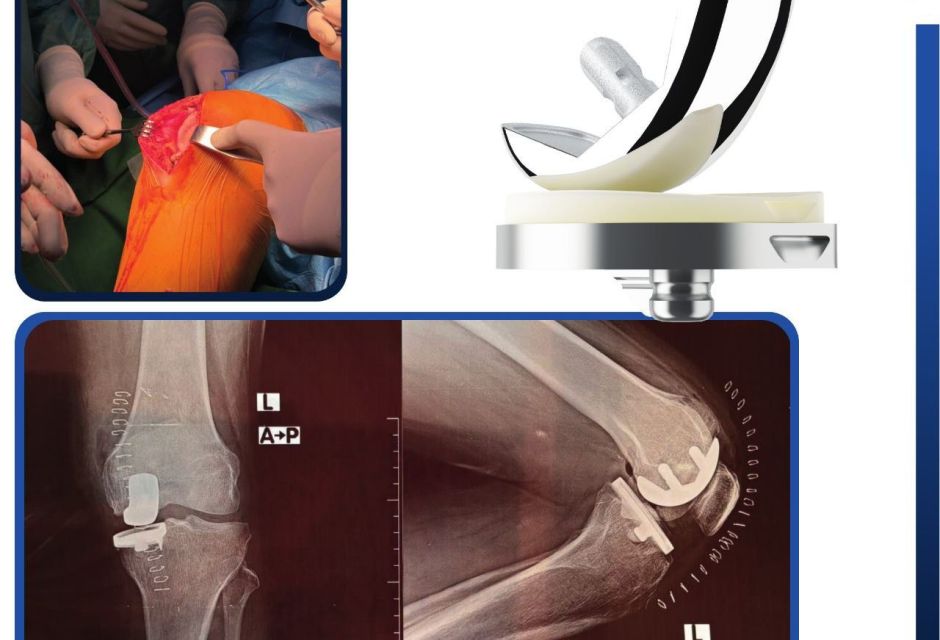

Keeping pace with the latest advancements in the health sector, and for the first time in Libya, three Partial Knee Replacement surgeries were successfully performed during the Fifth Knee Surgery Training Course, held in the city of Sabratha under the supervision of the Medical Specialties Board and the Libyan Society of Arthroscopy and Knee Surgery, at Al-Rasheed Hospital in Salah Al-Din.

This surgical procedure aims to replace only the damaged portion of the knee joint while preserving the healthy parts, and is used to treat unicompartmental knee osteoarthritis confined to a single compartment.